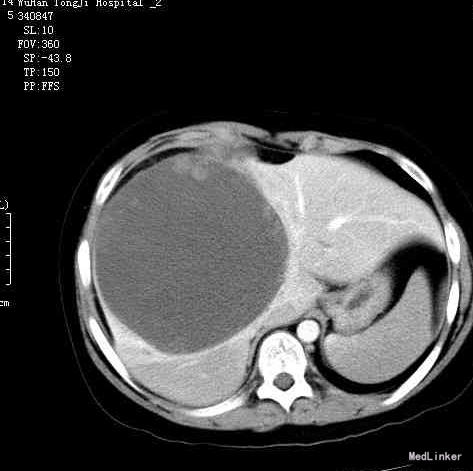

查体及辅查:他的全身体格检查无明显异常。他的皮肤或巩膜没有淡黄色的褪色,无蜘蛛痣和肝掌。系统检查显示大块肝肿大。他的血液计数和肝功能试验正常。甲胎蛋白也正常。超声检查显示,肝右叶有一个大肿块。他被转诊至本院进行进一步处理。对比增强CT扫描显示,肝右叶有一个大的低密度肿块,大小为14 cm × 15 cm × 15 cm

诊断:肝占位(肝ca?) 治疗:剖腹探查,发现肝右叶有一个大肿块,并且部分左叶包膜破裂,破裂部分粘附于胸膜。我们进行了肿瘤切除术,整个肝脏的大约70%被切除。对标本的病理学检查显示,肝右叶和部分肝左叶重1150 g,有1个大小为14 cm × 15 cm × 15 cm 的肿瘤块。组织学检测显示恶性肉瘤样组织,有巨大肿瘤细胞和残余肝细胞,提示肝未分化肉瘤(图2)。还存在重度不典型肉瘤组织,局部存在巨大细胞,部分细胞有成肌细胞的特点。磷酸烯醇式丙酮酸羧激酶(PCK)、波形蛋白以及α1抗胰蛋白酶的免疫组化染色为阳性,而上皮膜抗原(EMA)为阴性。